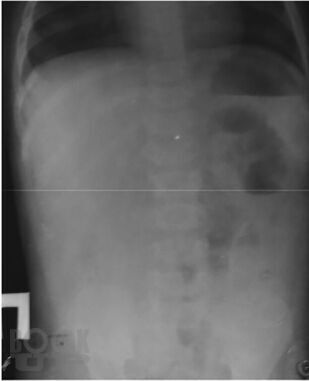

В монографии изложены наиболее актуальные вопросы диагностики и лечения кишечной инвагинации у детей. Представлены данные по истории вопроса, классификация заболевания, диагностический алгоритм. Рассмотрены наиболее частые ошибки в диагностике этого заболевания у детей, подробно обоснован выбор лечебной тактики на основании экспериментального;исследования безопасности консервативного лечения инвагинации кишечника в педиатрической практике. Описаны методики консервативного лечения этого состояния у детей, представлен анализ собственных практических результатов их применения. Отдельно рассмотрены вопросы оперативного лечения инвагинации кишечника у детей, приведено экономическое сопоставление методов лечения этого состояния.